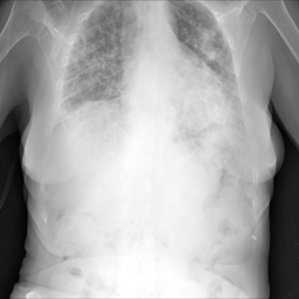

Samples of the dataset are depicted in Figure 3.

Figure 3. An example of an X-ray scan images taken from the dataset (a, b, c) with a label of COVID-19 negative, (d, e, f) COVID-19 positive.